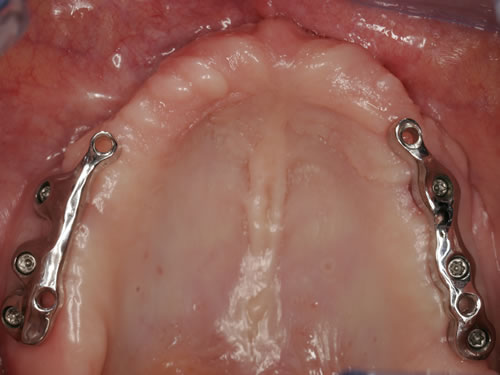

Für den Oberkiefer ist eine CT-Untersuchung notwendig, die ebenfalls mit einer Schablone durchgeführt wird. Auswertung, Planung und Implantations-Simulationen ergeben, dass sechs Implantate im vorderen Kieferabschnitt verankert werden können. Auch die Qualität des Knochens lässt eine Einpflanzung ohne weitere Maßnahmen zu. Diese Behandlung soll nach der Versorgung des Unterkiefers erfolgen.

Für den zahnlosen Ober- und Unterkiefer werden dies häufiger Stegkonstruktionen oder Teleskopversorgungen sein (Abb. 8.8 bis 8.16).

Abb. 8.10: Individueller Stahlsteg auf 4 Implantaten im zahnlosen Oberkiefer.